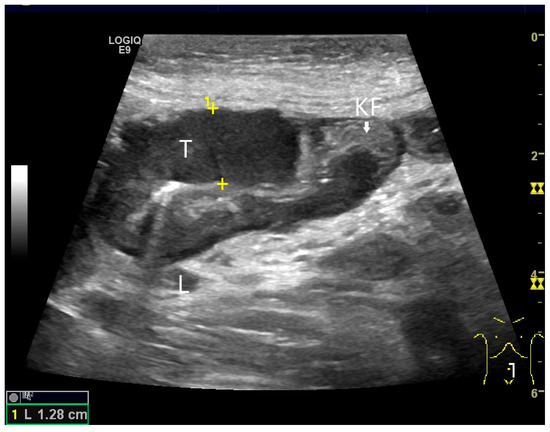

Figure 6.

Jejunal Adenocarcinoma. Segmental hypoechoic wall thickening (arrows) in the jejunum discovered during anemia diagnostics. Kerckring folds are faintly visible (KF) (a). Adjacent to this is a large round hypoechoic lymph node (L). The surrounding area shows hyperechoic changes (b).

Wu et al. [72] described a single adenocarcinoma in the jejunum using CEUS. The tumor is hypoechoic in B-mode, causing wall thickening and irregular borders. In CEUS, the tumor is hypoenhanced. Wu et al. also performed oral contrast enhancement with UCA [72]. The adenocarcinoma in Crohn’s disease is usually located in the distal jejunum or ileum. It is difficult to distinguish a pathological cockade due to a tumor from a transmural inflammatory wall thickening of Crohn’s disease. For diagnosis, clinical, imaging and laboratory data must be combined with a high degree of experience.